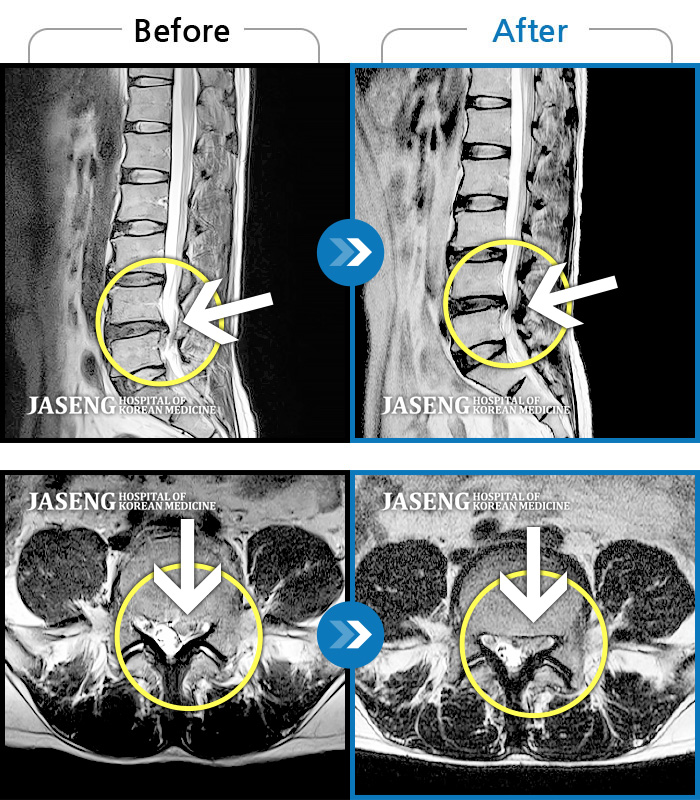

MRI 치료사례

재발한 허리디스크, 계속되는 요통 및 하지 방사통으로 내원